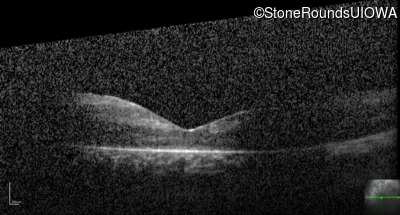

Optical Coherence Tomography - Right - 20/80 -1

Exemplar / OCT Stack

OCT Stack